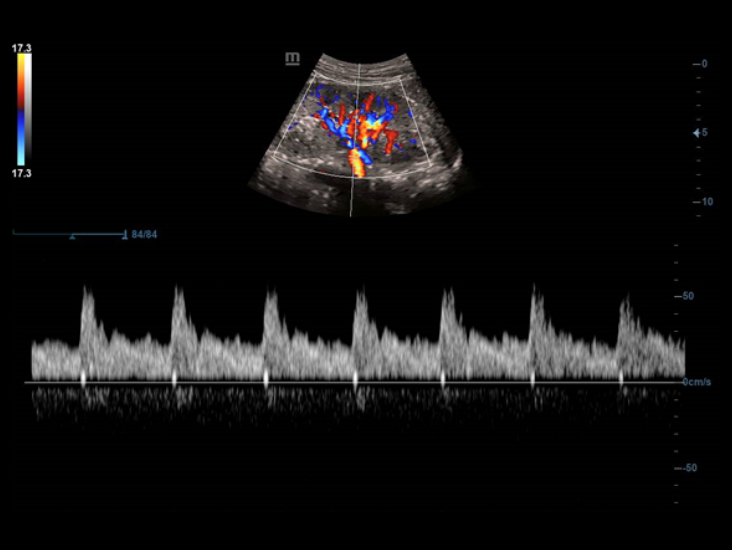

Smart Track

Smart Track proporciona una optimizaciĂłn rĂĄpida e inteligente de imĂĄgenes vasculares con un sencillo manejo de un solo toque. Puede optimizar el espectro de Color, Potencia y PW mediante seguimiento automĂĄtico y reducir pasos que llevan tiempo. Por lo tanto, el flujo de trabajo del examen vascular se simplifica con una Ăłptima visualizaciĂłn.